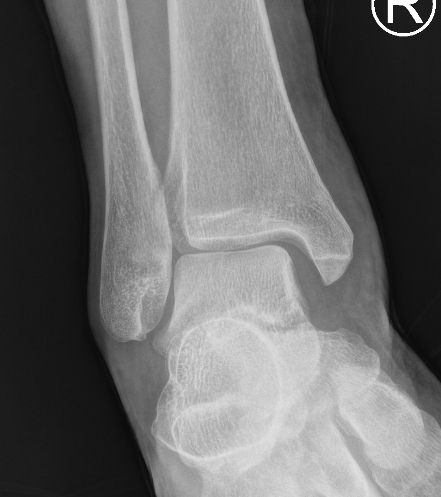

四級韌帶撕裂

| 病徵: 四級踝關節扭傷屬於嚴重病例,韌帶斷裂,踝關節半脫位。症狀包括劇烈疼痛、腫脹、踝關節不穩定和行走困難。 |

| 腫痛 |

距骨移位 |

選擇1: 手法復位+石膏固定+短身步行靴(A16b)

「手法復位」後,需用石膏固定3週,並進行X光檢查以確保沒有半脫臼。之後,受傷的踝關節可繼續以石膏固定大約3週,靜止休養,促進癒合。隨後使用短身步行靴(A16)進行大約3週的復健治療,所有治療期間需使用拐杖,避免足踝負重所導致的疼痛及半脫臼,並在拐杖的輔助下進行階段性康復,漸進式負重。